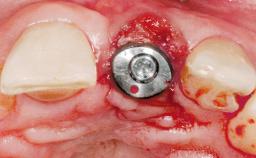

Immediate Flapless Placement of an Implant in a Maxillary Left Central Incisor Site

A 42-year-old female patient was referred to our clinic at the School of Dentistry of the University of São Paulo in November 2004, presenting a deficient restoration in the upper left central incisor. The clinical examination revealed no gingival retraction or any signs of gingival inflammation and, therefore, previous periodontal treatment was not considered. The patient presented a high lip line at full smile and a thin tissue biotype. This combination characterized a high-risk situation from an anatomic point of view, which required careful preoperative planning and cautious surgical execution.

| Placement Protocol | Immediate implant placement |

| Socket Morphology | Single-root socket |

| Socket Integrity | Sufficient, with intact bone walls |

| Bone Volume | Sufficient, with intact walls |